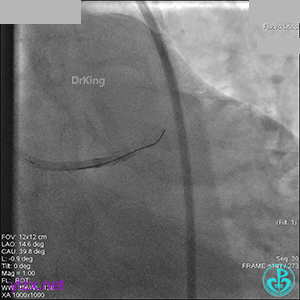

先处理前降支开口严重狭窄并顺利植入前降支到左主干支架。

没有说明是否进行了右冠脉介入治疗。